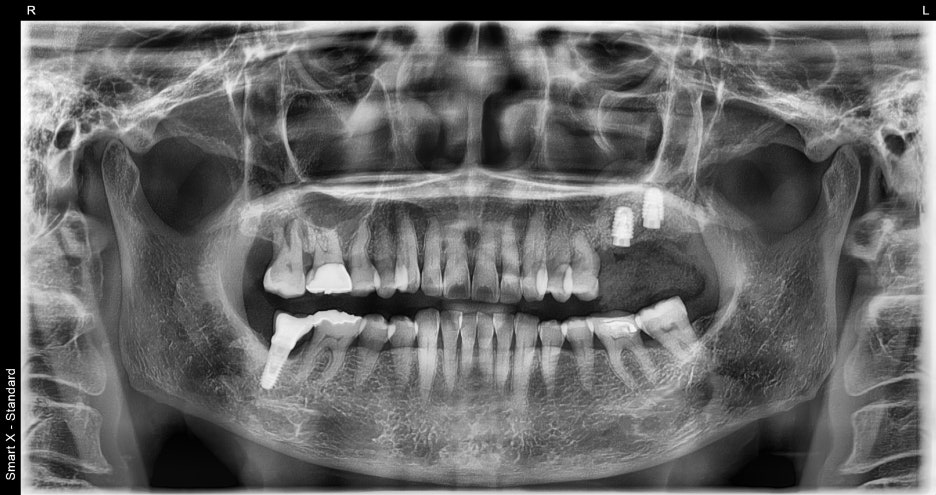

③ Prosthetic fabrication and placement

– In the in-house dental laboratory, we fabricated a custom zirconia crown to match the color of the patient’s other teeth.

– We adjusted the occlusion (bite) and placed it so the patient could chew naturally and comfortably.

Before and after treatment photos

If chewing is difficult because of a fractured tooth like in this patient,

implant treatment is possible after an accurate diagnosis regardless of age. Seoul Orbit Dental Hospital, based on university-hospital-level equipment and a system of joint care with specialists,

helps elderly patients receive implants safely.